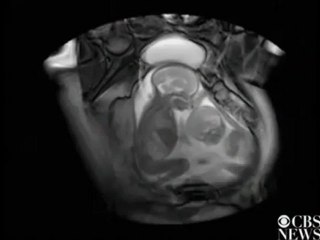

Lucky TWINS Shibuya WOMB